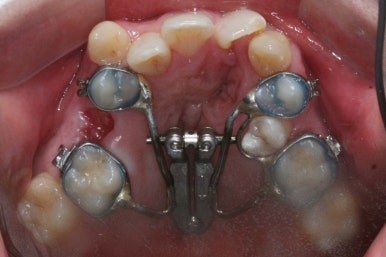

부산구순구개열 키다리아저씨치과에 처음 오셨을 때의 입 안의 모습입니다.

입천장이 갈라져서 어릴 때 봉합 수술을 했기 때문에 그 상처가 굵게 남아있는 것을 볼 수 있습니다. 일반적으로 피부상처도 다른 부위보다 단단하듯이 입천장의 봉합 상처도 매우 단단하게 아물기 때문에 성장에 방해를 주게 됩니다.

가로폭이 매우 좁고 찌그러져 있습니다.

또한 위턱이 앞으로 자라나는 것도 방해해 대부분 앞니가 거꾸로 물리게 됩니다.

또한 가랄져 있던 선에 걸쳐 있는 영구치 일부는 선천결손이 되는 경우가 많습니다.

이번 환자분도 이런 특징을 모두 갖고 계셨습니다.

좁아져 있는 위턱뼈를 가로로 넓혀주기 위해서 악궁확장장치를 사용했습니다.

악궁확장이 시작될 시점과 악궁확장을 다 진행했을 시점의 비교입니다.